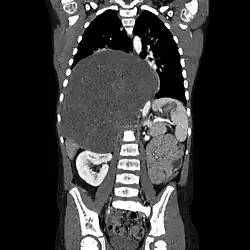

| CT scan of a large ganglioneuroma within the chest cavity | |

Ganglioneuromas can be diagnosed visually by a CT scan, MRI scan, or an ultrasound of the head, abdomen, or pelvis. Blood and urine tests may be done to determine if the tumor is secreting hormones or other circulating chemicals. A biopsy of the tumor may be required to confirm the diagnosis.[4]